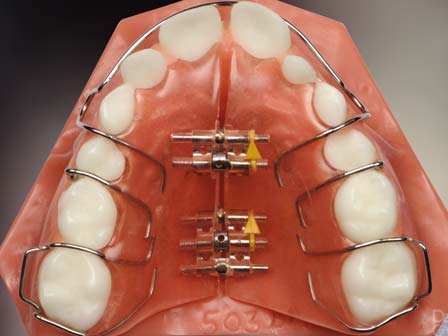

منظور از ارتودنسی با دستگاه متحرک این است که بیمار می تواند دستگاه ارتودنسی را از دهان خارج کند. ارتودنسی متحرک شامل دو دسته کلی می شود یک گروه عبارتند از پلاک های متحرک ساده برای حرکات جزئی دندانی و گروه دیگر شامل پلاک متحرکی که برای رفع ناهنجاریهای فکی مانند عقب بودن فک پایین یا بالا به کار می رود. از دستگاههای متحرک برای مرتب کردن دندانها در شرایطی استفاده می شود که یا بی نظمی دندانها کم است و در ضمن سن بیمار برای انجام درمان ارتودنسی ثابت کم می باشد .

به عبارت دیگر دندانهای شیری با دندانهای دائمی جایگزین نشده اند . از سوی دیگر دستگاههای متحرک برای جابجایی فکین نیز به کار برده می شود. این دستگاهها برای جلو آوردن فک پایین و یا جلو آوردن فک بالا براساس نیاز بیمار به کار برده می شوند . پلاک متحرک می تواند به صورت مستقل و یا به همراه ارتودنسی ثابت به کار برده شود .